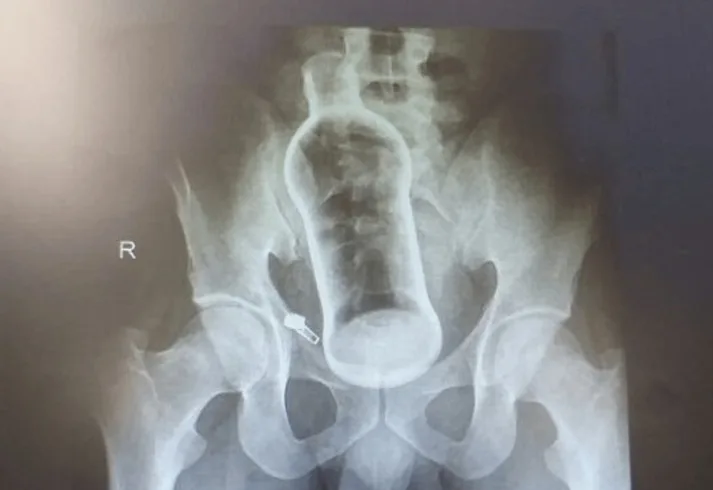

Пациент поступил в отделение неотложной помощи в стабильном состоянии. Несмотря на отсутствие психических диагнозов и жалоб, это было не первое подобное происшествие в его жизни. В ходе обследования врачи обнаружили в прямой кишке мужчину стеклянную ёмкость длиной около 10 сантиметров, которая стала причиной внутреннего дискомфорта.

Для извлечения инородного предмета медики применили метод трансанальной экстракции — операцию удалось провести без разрезов, с помощью правильного позиционирования пациента и внешнего давления на живот. Полостное вмешательство не потребовалось.